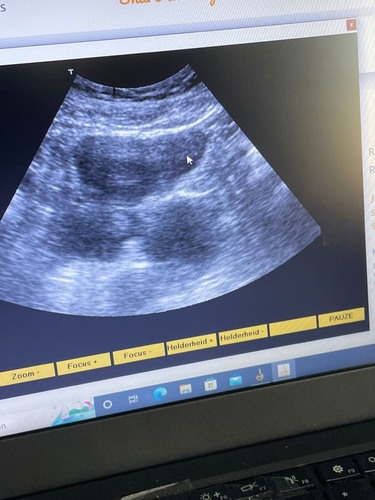

Ik zie niks. Er valt ook niets te zien met 6 weken.

Met 6 weken kan je nog zo weinig zien! Zelf ook een vroege echo gehad, dat was voor de verloskundige al zoeken laat staan als je het zelf doet. Boek een vroege echo bij een verloskundige als je graag iets wilt zien (wat ik snap, ik wilde dat ook!) en breng dit apparaat snel terug naar je vriendin 🙈.

Daarnaast zijn die huurbare apparaten echt van te slechte kwaliteit om met deze termijn al iets te zien. Ze doen niet voor niks een inwendige echo bij deze termijn.

De kwaliteit van de echo is erg slecht. Ik kan hier niets uit opmaken. Op deze termijn bij de verloskundige zal er vaak al een kloppend hartje te zien zijn.